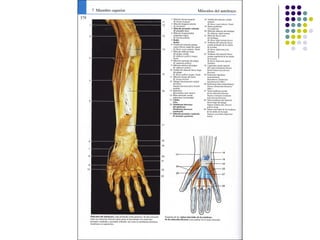

La extremidad superior humana incluye el hombro, el brazo, el codo, la muñeca y la mano. Está diseñada para una variedad de funciones motoras finas como agarrar objetos y realizar tareas manuales complejas. La coordinación precisa de los músculos y los huesos de la extremidad superior es clave para su versatilidad funcional.